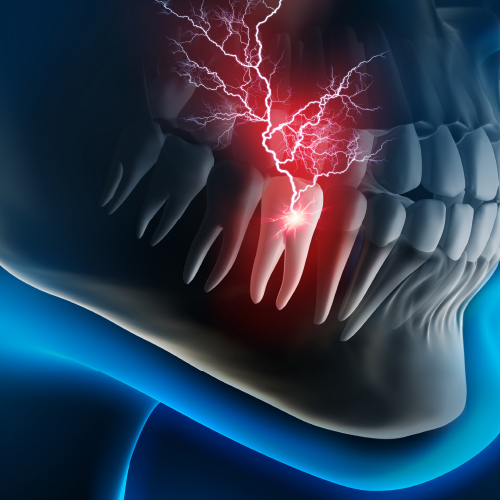

New Directions in Endodontics

Tuesday, April 2, 2024

This Compendium eBook features a continuing education (CE) article on the management of endodontic flare-ups. This eBook also includes an article on intentional replantation as a predictable and cost-effective option for preserving a natural tooth and as a favorable alternative to conventio...